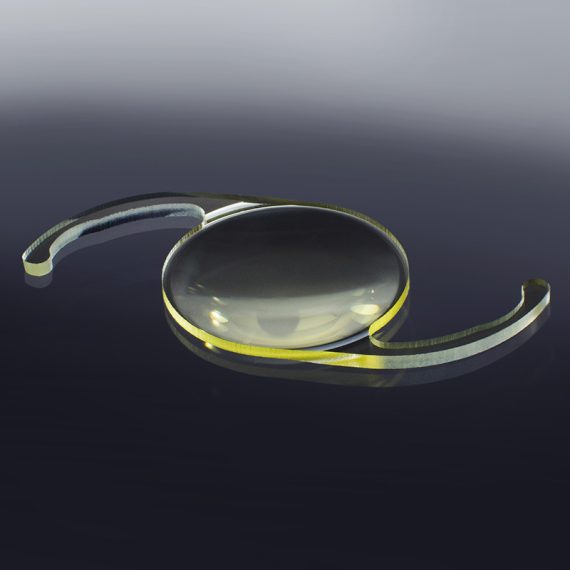

MBI PreciSAL™ monofocal IOLPrecision creates perfection. MBI created Precision Soft Acrylic Lenses...Code: SALP302A, SAL302AExplore

MBI PreciSAL™ monofocal IOLPrecision creates perfection. MBI created Precision Soft Acrylic Lenses...Code: SALP302A, SAL302AExplore -

MBI PreciSAL™ toric IOLYour choice is clear. MBI PreciSAL Toric lenses correct...Code: SALPT302AExplore

MBI PreciSAL™ toric IOLYour choice is clear. MBI PreciSAL Toric lenses correct...Code: SALPT302AExplore -